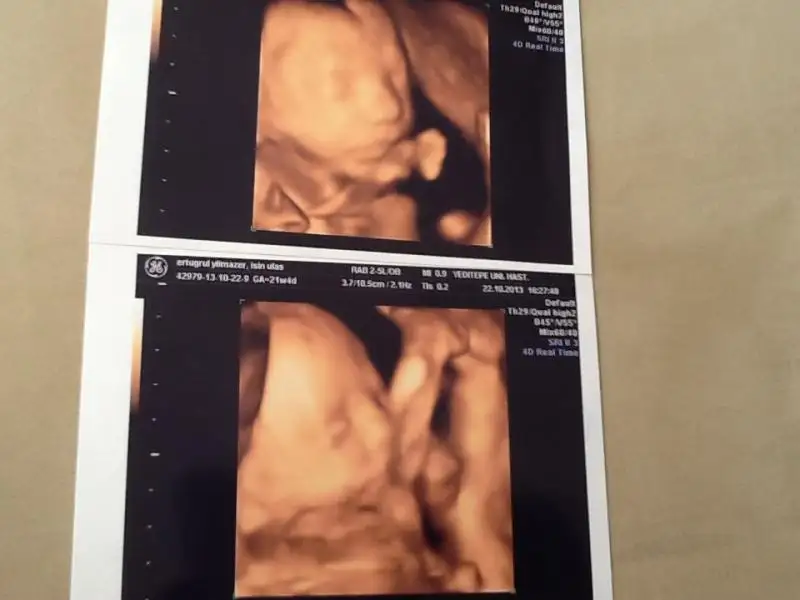

İşte benim kuzucuk. İkinci fotografta ayaklar nerede bir bakar mısınız...

oyyy kuzucuk oyyy,içim eridi resmen keyfi yerinde akrobatcan/akrobatgül'ün :))) Allahım nazarlardan korusun çok güzel çookk.. Coşkun coşkum oldu fotoyu görünce:))

o bacaklardan anladığım kadarıyla mesleği belli olacak onun o bacaklar kafaya kadar gelebildiyse kesin jimlastik yapar bu güzellik:))

ayy şu şirin şeye bak seeenn ayaklar nerde